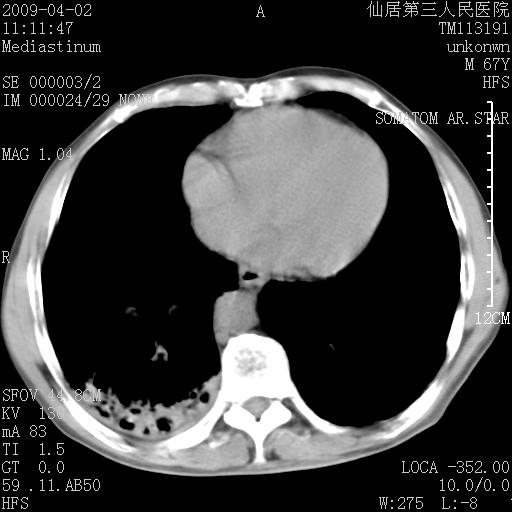

患者老年男性,乏力畏寒来诊,摄胸片示右下肺感染性病变,抗炎两周后复查胸片,无好转有进展。

后做ct平扫表现如下:

病灶呈蜂窝征,纵隔多个淋巴结肿大;肺泡癌需考虑

标题: 干酪性肺炎

右肺下叶背段干酪性肺炎。请痰检[emb28]

我认为普通的感染应该可以除外,间质性肺炎可能性较大,但如何解释纵膈的淋巴结肿大呢

考虑双肺间质性改变(间质纤维化?)伴右肺下叶感染。

支持11楼,考虑肺结核.年䶨;大,抗炎无效.纵隔淋巴结肿大.老年人下肺结核要警提